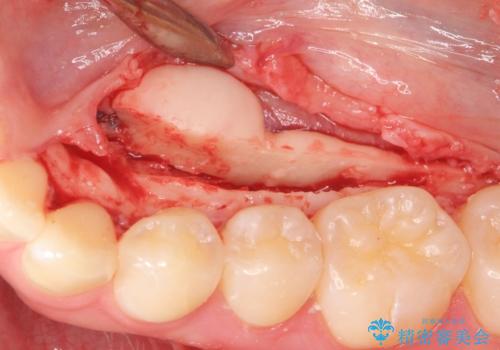

- 舌が下顎の骨隆起にあたって不快との事で来院。

静脈内鎮静麻酔を行い下顎骨隆起切除術を行いました。

骨隆起がなくなり舌が当たるストレスがなくなり大変満足していただけました。

反対側の骨隆起も切除を行う予定です。